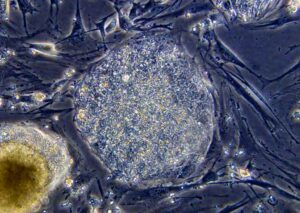

I ricercatori stanno attualmente studiando le cellule staminali embrionali per determinarne il potenziale utilizzo nelle terapie rigenerative basate sulla sostituzione cellulare, perché hanno la capacità di auto-rinnovarsi e svilupparsi in una varietà di tipi di cellule e tessuti come ad esempio le cellule ematiche, i neuroni, le ossa e i muscoli.

Gli scienziati riconoscere tuttavia che i cambiamenti genetici si verificano in un certo numero di linee di hESC quando si moltiplicano in laboratorio, e questi cambiamenti possono assomigliare alle anomalie del DNA (acido desossiribonucleico) spesso presenti nelle cellule tumorali. Le hESC potrebbero inoltre subire altri cambiamenti genetici che i metodi tradizionali non riescono a rilevare. Ne risulta che nel mondo della medicina permangono gravi preoccupazioni riguardo al loro impiego.

Il team ha utilizzato l’analisi del DNA ad alta risoluzione per mappare le modifiche genetiche in 17 linee di hESC coltivate per molte generazioni e conservate in laboratori diversi. La loro analisi ha individuato 843 variazioni del numero di copie (CNV), e “in media, il 24% dei siti con perdita di eterozigosi (LOH) e il 66% delle CNV cambiavano durante la coltura, tra il passaggio precoce e tardivo della stessa linea”, hanno scritto gli autori. Le CNV e LOH sono variazioni genetiche che potrebbero essere legate alla trasformazione tumorale. I ricercatori hanno scoperto che il 30% dei geni con siti CNV aveva “un’espressione alterata rispetto ai campioni con un numero di copie normale, di cui oltre il 44% erano funzionalmente collegate al cancro”.